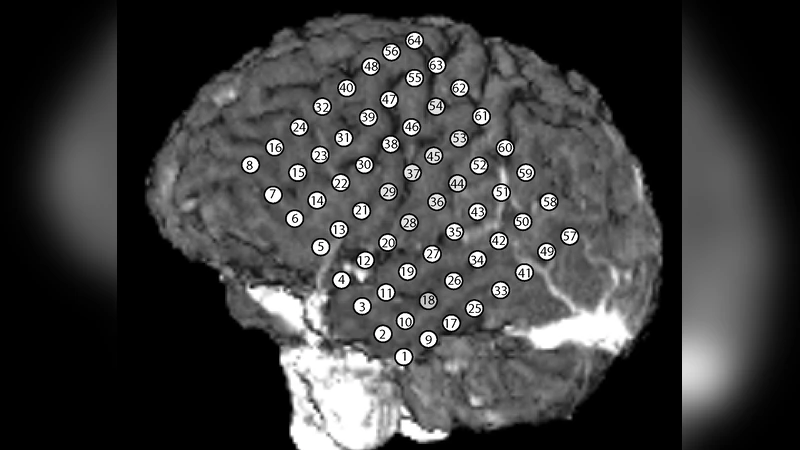

ECoG 데이터 적용에서는 64채널 기록을 1초 윈도우로 나누어 위상 추출 후, 행동(휴식 vs. 작업) 별 K 행렬을 비교하였다. 작업 상태에서는 전전두엽과 측두엽 사이의 κ 값이 유의하게 증가했으며, μ 값은 특정 주파수 대역(θ, α)에서 일관된 위상 선행을 나타냈다. 이는 행동에 따른 기능적 연결성 변화를 위상 기반 통계로 정량화할 수 있음을 시사한다.